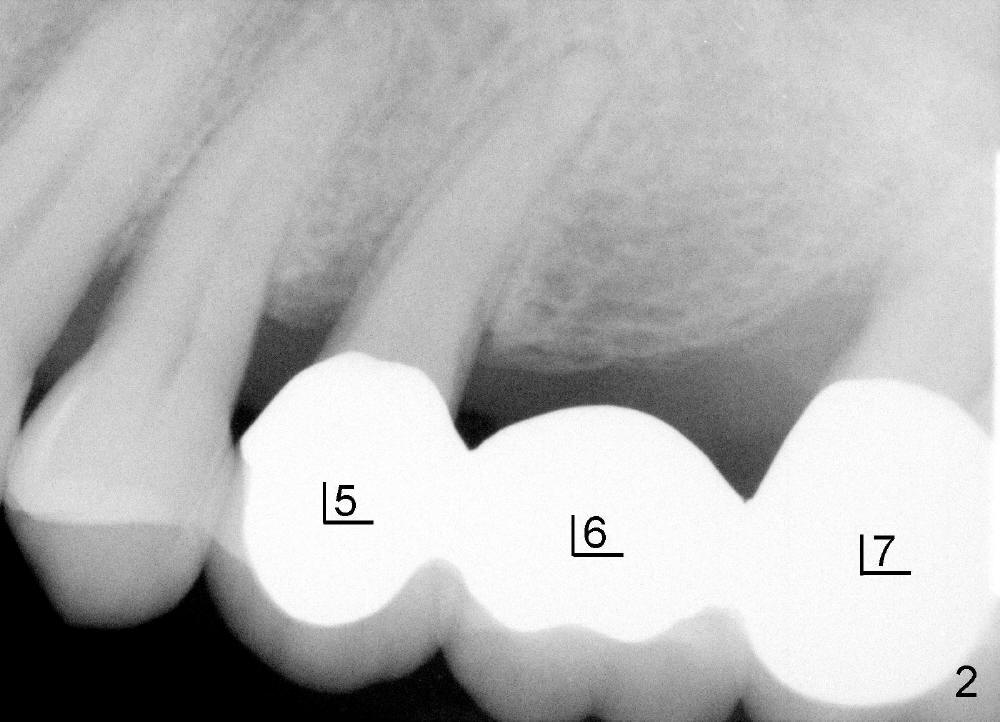

五十来岁郑先生有两个主诉:第一,左上桥松动(图二,五),要求拔除后面基牙;第二,右下六号牙处需要植牙(图三)。初步检查几张根尖片(图一至五),他是典型牙周病病人,悲观人认为不治之症,乐观人却认为这是最好植牙病例,虽然骨质吸收严重,但是剩下骨质坚硬,因为牙周病病人往往咬合力很大。充分利用剩余骨质吧。现在他口腔卫生不差。

病人要求先处理左上桥(图二,五),我们准备在五六号牙之间切断桥(图六:黑线),拔除七号牙,立刻植牙。那里骨头高度多少?是黑线,还是红线?一两天我们就会给您答复。估计在那里可以植入七或者八乘十一或者十四毫米植牙。

如果时间允许,我们可能同时在左上六号牙处植牙,骨头高度好像不乐观(图五,六),积极人在图二找骨头,估计可以植入六乘十一或者十四毫米植牙。